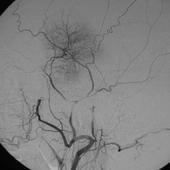

间接型颈动脉海绵窦瘘

628健康网为您分享有关间接型颈动脉海绵窦瘘的症状,间接型颈动脉海绵窦瘘的治疗方法,间接型颈动脉海绵窦瘘的预防知识...

硬脑膜动静脉畸形

628健康网为您分享有关硬脑膜动静脉畸形的症状,硬脑膜动静脉畸形的治疗方法,硬脑膜动静脉畸形的预防知识,硬脑膜动静脉畸...

自发性蛛网膜下腔出血

628健康网为您分享有关自发性蛛网膜下腔出血的症状,自发性蛛网膜下腔出血的治疗方法,自发性蛛网膜下腔出血的预防知识...